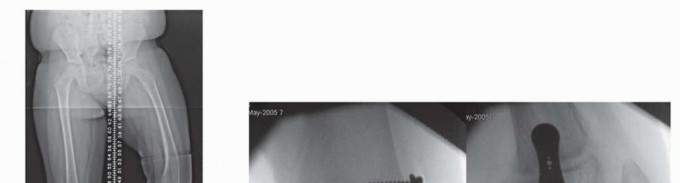

- FIG 2 • A. A 13-year-old girl with knee pain and difficulty with ambulation secondary to genu valgum. B. Standing AP radiograph of her lower extremities demonstrating bilateral genu valgum with abnormal LDFA bilaterally and an abnormal MPTA on the right tibia. She was indicated for bilateral medial distal femoral

- guided growth and right medial proximal tibia guided growth. C. Standing AP radiograph at 7 month postoperatively demonstrates normalization of her mechanical axis. (Courtesy of UW Pediatric Orthopaedics.)

- FIG 5 • A. An 8-year-old boy with 20 degrees residual equinus and talus dysmorphology after revision posterior medial release. B,C. Anterior distal tibia guided growth was performed after a CT scan ensured appropriate sizing of the epiphysis. In this procedure, a modular implant is placed by putting a guide pin into the distal tibia epiphysis and then a cannulated screw is placed. D,E. Two years postoperatively, the patient now has 10 degrees of ankle dorsiflexion. (Courtesy of UW Pediatric Orthopaedics.)